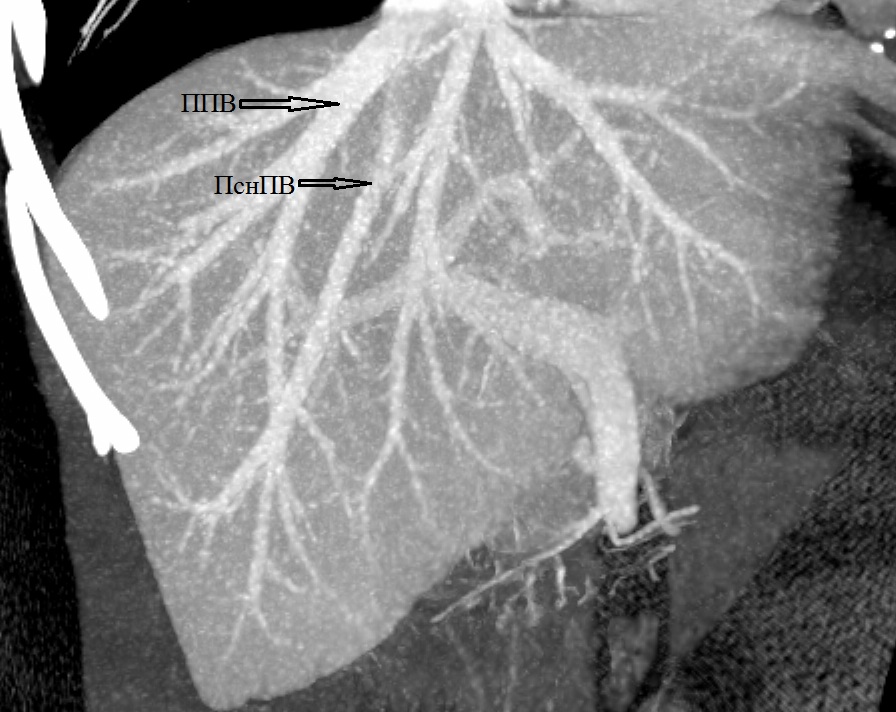

5. Тип B (схема). | |

| Тема | ||

| Тип | Исследовательские инструменты | |

Посмотреть

(1MB)

|

Метаданные ▾ | |